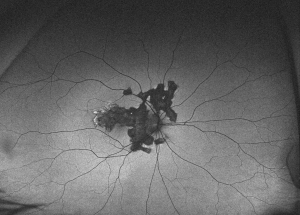

SC presents with gray-yellowish subretinal infiltrates that usually spread centrifugally from the peripapillary region in a serpiginous (snake-like) manner. Active lesions show a leading edge and resolve with subsequent RPE and choriocapillary atrophy. Consecutive recurrences cause further atrophy leaving hypo- and hyper-pigmented lesions that spread irregularly over the posterior fundus. Although bilateral, the disease is often asymmetric with multiple lesions in different stages of resolution in both eyes. ecurrences have variable intervals that range from months to years. Anterior chamber and vitritis are minimal. [4]

Ancillary testing in SC include fluorescein angiography (FA), indocyanine green angiography (ICG) and fundus autofluorescence (FAF). In active lesions occurring at the margins of an atrophic lesion, FA typically shows early hypofluorescence with late leakage. As in other inflammatory choroidopathies, ICG is characterized by hypofluorescent areas from early to late frames.[4] FAF has become increasingly useful and a minimally invasive tool for monitoring disease progression in SC. [6] Active lesions show a hypoautofluorescent halo surrounding the edges of a hyperautofluorescent lesion. Semi-active or transitional lesions show a linear hypoautofluorescence surrounding all edges of the hyperautofluorescent lesion. Quiet or inactive lesions are dark and uniformly hypoautofluorescent.